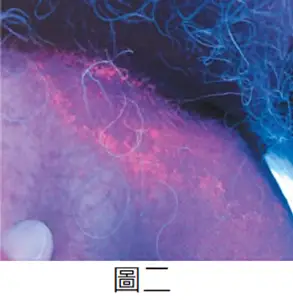

- 圖二(伍氏燈檢查):

- 觀察:在紫外線(UV light)照射下,病灶呈現鮮明的珊瑚紅(coral-red)或磚紅色螢光。

- 意義:這是紅癬(Erythrasma)的病理性特徵(pathognomonic sign)。此螢光來自於致病菌 Corynebacterium minutissimum 所代謝產生的卟啉(porphyrins),特別是 coproporphyrin III。

患者長期流汗且病灶位於胯下,臨床鑑別主要在於黴菌感染與細菌感染。圖二伍氏燈檢查顯示的「珊瑚紅螢光」是**紅癬(Erythrasma)**的特異性表現,直接排除了股癬(無螢光)與念珠菌感染(無此顏色螢光)。紅癬是由細菌 Corynebacterium minutissimum 感染角質層所致,該菌產生的 Coproporphyrin III 在 UV 光下會發出特徵性的紅色螢光。